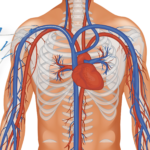

SpireWire® Fil de guidage PTCA Chirurgie cardio-vasculaire

Urologie cardiologie interventionnelle

cardiologie interventionnelle Gynécologie Obstétrique